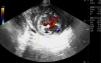

La miocardiopatía no compactada es una entidad poco frecuente asociada a complicaciones como insuficiencia cardiaca, fenómenos cardioembólicos, arritmias y muerte súbita. De etiología del todo no aclarada, presenta una base genética. Su diagnóstico está aumentando debido al uso de la ecocardiografía, y se caracteriza por el engrosamiento de la pared del ventrículo izquierdo con prominencias y recesos con ausencia de compactación del miocardio, diferenciándose dos capas: miocardio compactado y no compactado (fig. 1). Es característico visualizar en Doppler color de flujo sanguíneo entre dichas criptas sin comunicación con el sistema coronario (figs. 2 y 3), pudiendo originar embolias.

Aportamos imágenes ecocardiográficas de una mujer de 62años con clínica de insuficiencia respiratoria secundaria a EAP en el contexto de disfunción ventricular (vídeo)